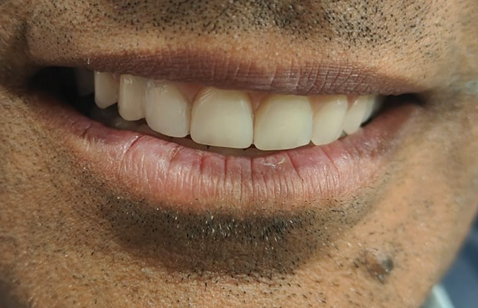

The patient left with a confident smile once again.

The patient left with a confident smile once again.